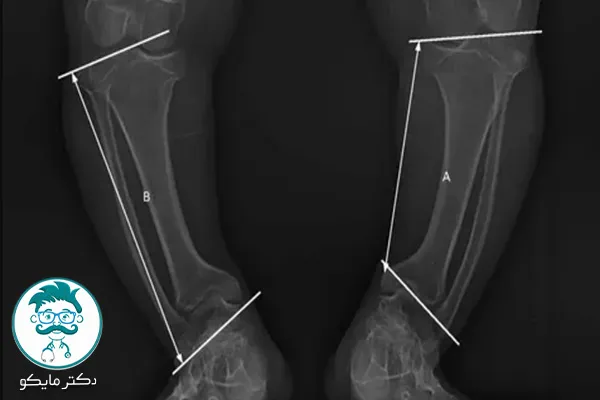

در پاهای پرانتزی خفیف، معمولاً فاصله بین زانوها کم است و این مشکل به راحتی قابل تشخیص نیست. برای تشخیص وضعیت دقیقتر، استفاده از عکسهای رادیولوژی میتواند به شناسایی میزان انحراف پاها کمک کند. در تصاویر رادیولوژی، ممکن است زاویه و فاصلهی میان زانوها به وضوح قابل مشاهده باشد.

عکس پای پرانتزی و سالم

برای مقایسه وضعیت پای پرانتزی با پاهای سالم، تصاویر رادیولوژی میتوانند مفید باشند. در پاهای سالم، باید زاویه بین ساق پا و ران تقریباً صفر باشد. در صورتی که زاویه انحرافی وجود داشته باشد، نشاندهندهی مشکل پا پرانتزی است.

- چک کردن عکسها: در برخی موارد، عکسبرداری از پاها به کمک پزشک یا رادیولوژیست میتواند به شفافسازی مشکل کمک کند.

اگر زاویه انحراف پا در عکسها کمتر از ۱۵ درجه باشد، معمولاً به عنوان پای پرانتزی خفیف شناخته میشود. در این حالت، درمانهای غیرجراحی و تغییرات سبک زندگی میتوانند مؤثر واقع شوند.